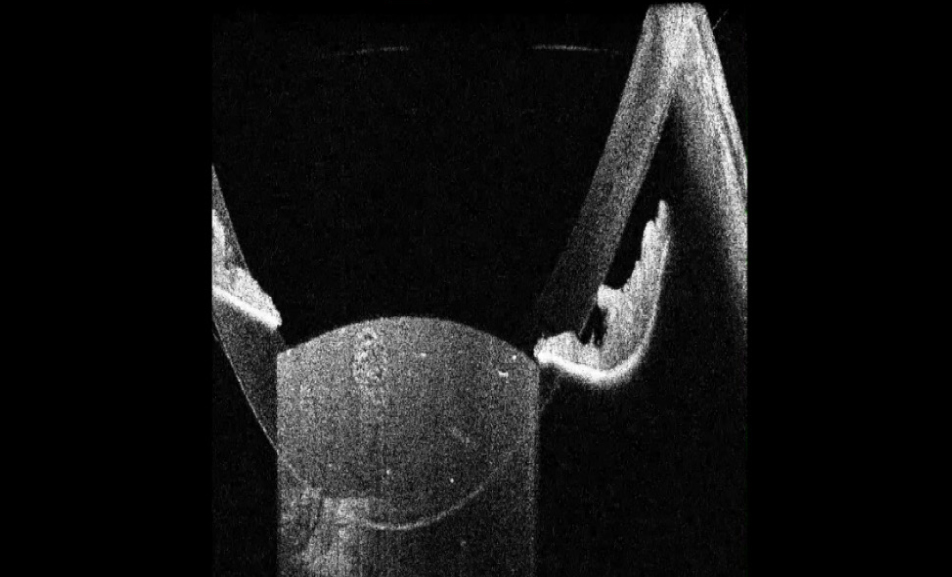

В исследование вошли 196 пациентов (250 глаз) с перезрелой катарактой. Пациенты были разделены на 2 группы (по 125 глаз в каждой группе). Всем пациентам интраоперационно с помощью интегрированной в операционный микроскоп И-ОКТ, Hi-R NEO (HAAG STREIT, Германия), определяли тип перезрелой катаракты (рис. 1–4).

Рис. 1. Тип 1 перезрелой катаракты: равномерно расположенные кортикальные волокна, минимальные внутрихрусталиковые щели, отсутствие оводнения кортикальных масс